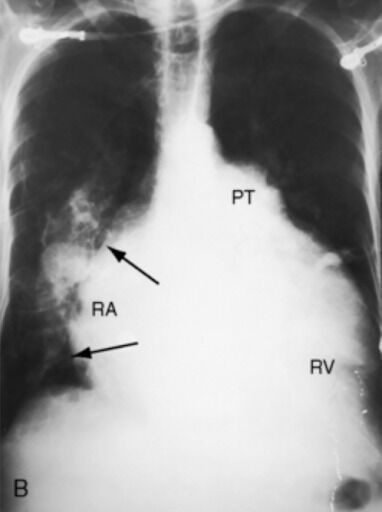

Quais são os achados radiológicos do aumento do AE? abaulamento lateral em PA e abaulamento posterior em perfil (coração mais redondo em cima)

Quais são os achados radiológicos do aumento do VE? borda inferior deslocada para o lado e ápice para baixo em PA, coração se projetando para trás em perfil (coração mais pontudo p baixo)

Quais são os achados radiológicos do aumento do AD? projeta-se mais para a direita e alarga-se +Cefalização do fluxo pulmonar (IC esquerda e estenose mitral) +Linhas B de Kerley (ao edema intersticial)

O que é o Sinal da borboleta? Quais são suas características radiológicas? Opacidade alveolar bilateral em campos pulmonares médios. -Diminuição simétrica da transparência pulmonar perto do hilo, poupando periferia -Significa edema alveolar extenso em edema agudo de pulmão/ICC. -Infiltrado que preserva a periferia.